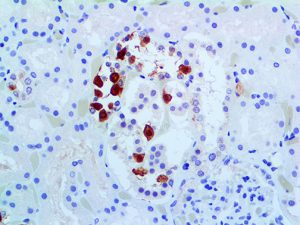

Clinical and laboratory manifestations of HLH include fever, enlarged liver and/or spleen, neurologic dysfunction, coagulopathy, liver dysfunction, cytopenias (i.e., low levels of erythrocytes, leukocytes, and/or platelets), hypertriglyceridemia, hyperferritinemia, hemophagocytosis, and eventually diminished NK cell activity as the immune system becomes progressively paralyzed. HLH can be familial (primary HLH) or secondary to another disease process (sHLH), such as rheumatic disease, in which it is referred to as macrophage activation syndrome (MAS, characterized by elevated ferritin).